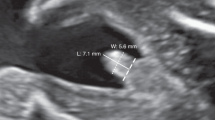

Amino acids in the blood spot filter paper card may degrade over time, thus we studied whether this had an effect on Phe levels. Regression analysis of Phe levels against time from collection to analysis (Fig. 2) showed a slight decline of the Phe with increased time since collection (0.004 µmol/L per day; p = 0.003) manifesting as a 4-µmol/L decrease for samples analyzed at 1000 days. Adjusted Phe levels were then created using the expression: adjusted Phe (mmol/L) = Phe (mmol/L) + [(days from collection – 63) × 0.004].

Phenylalanine (left) and tyrosine (right) levels from dried blood spot cards using tandem mass spectrometry, plotted by time from collection to time analyzed, in days. Plots for first (1), second (2), and third (3) trimester are shown, along with a composite of all values from all trimesters (total). Line and gray shading indicate fitted linear regression line and 95% confidence intervals.